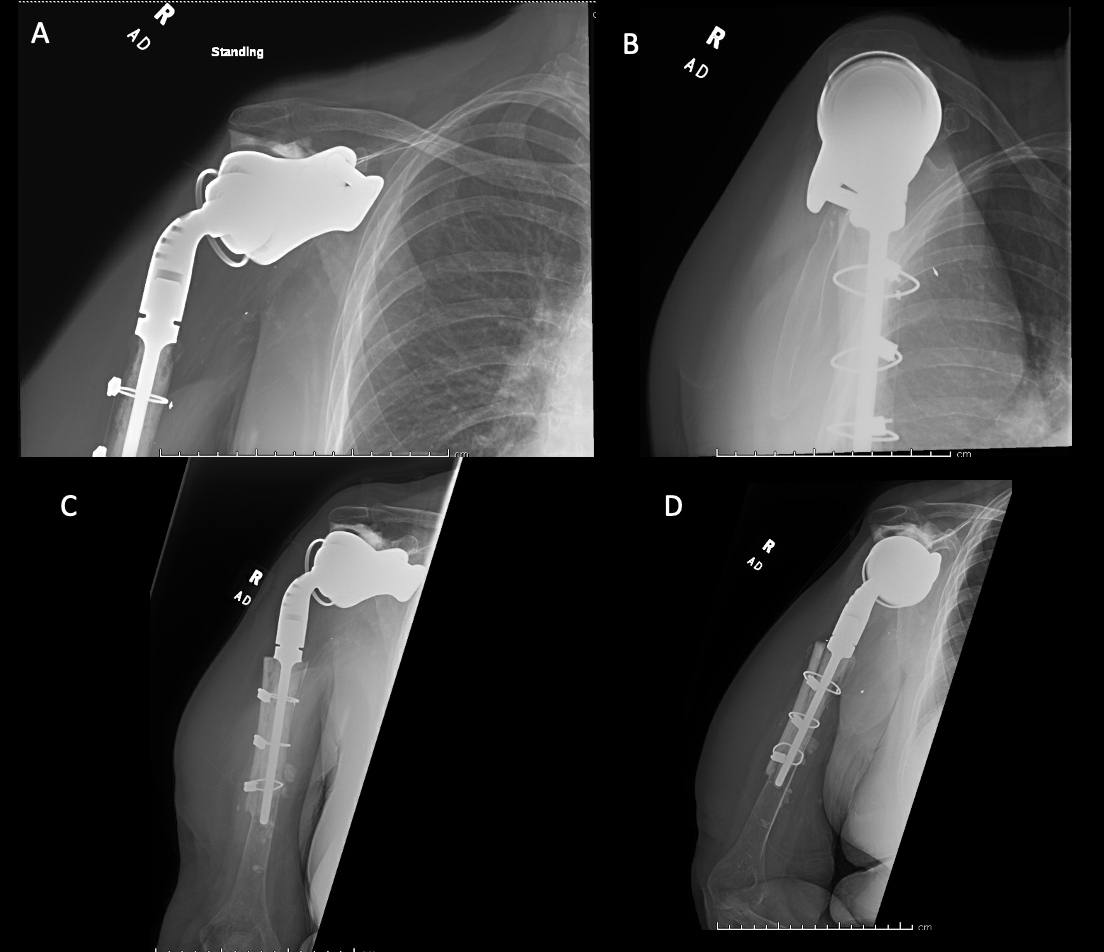

Case 1. At the latest follow-up one-year post-op, patient 1, who had the more extensive humeral exposure, was extremely pleased with the results of the surgery despite occasional pain. She had resolution of an early post-op radial nerve palsy. She could button up her blouse and get her hand to her mouth. Her shoulder and scapular x-rays showed some new radiolucency between the superior aspect of the glenoid prosthetic component and the associated bone cement in the subacromial space (Figure 13). At 2 years post-op she continues to have significant pain relief and has maintained her active range of motion (AROM). Elbow AROM was from 10 to 145 degrees. Shoulder AROM was abduction to 15 degrees and internal rotation allowing the hand to reach the level of L5/S1 vertebrae.

Case 2. At the latest follow-up one-year post-op, the patient expressed that the pre-operative pain had resolved after the operation. Despite this, she stated that if given the option again she would not undergo the surgery because she did not attain the function she expected and felt that her function may have decreased compared to pre-op. Overall stability and alignment were good. On physical exam, she was able to reach within 1 inch from her mouth and had 20 degrees abduction and 5 degrees forward flexion actively. Active elbow flexion was 0 to 120 degrees (Figures 14). At 2 years post-op she had some regression in her pain but accompanied by modestly decreased AROM. Shoulder AROM was 15 degrees abduction, and 5 degrees forward flexion. Elbow AROM was from 0 to 105 degrees of elbow flexion. CT scan showed increased lucency surrounding the humeral component concerning for osteolysis and prosthesis loosening (Figure 14). Blood work at the 2-year mark to investigate the radiolucencies and decreased AROM left us with low suspicion for infection (WBC 5.4, ESR 33, CRP <3.0).